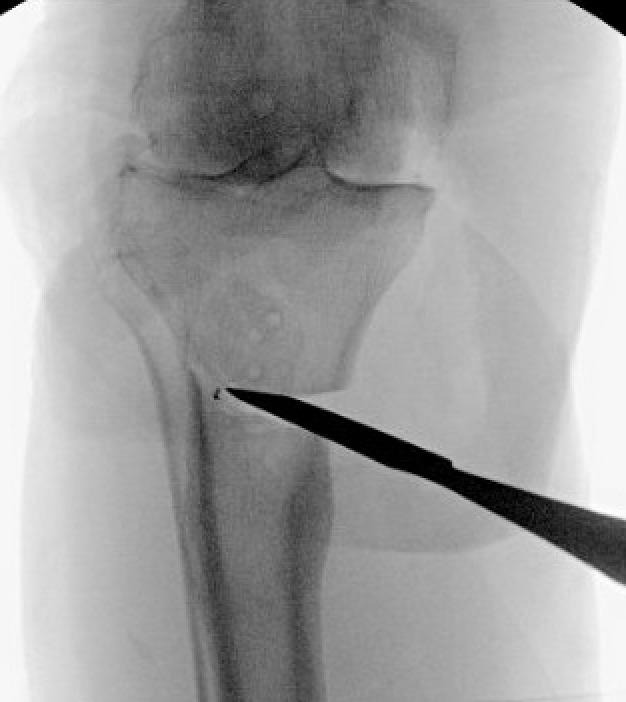

Pre-operative radiographs demonstrated Kellgren-Lawrence grade 4 tricompartmental osteoarthritis, 12° of tibial varus, a 22 mm deviation of the mechanical axis toward the medial side of the knee center, and an apex of angulation located 6 cm below the joint line (Figures 1 and 2). A follow-up computed tomography scan confirmed the absence of rotational malunion.

The two TTO cortical screws were removed. Attention then turned to the extra-articular deformity. Under biplanar fluoroscopic control an oblique medial open-wedge osteotomy was created six centimeters distal to the tibial plateau at the apex of the varus malunion (Figure 3). A laminar spreader was gently inserted and opened until a neutral mechanical hip–knee–ankle axis was achieved, as confirmed with an extramedullary alignment rod extending from the center of the femoral head to the center of the ankle mortise.